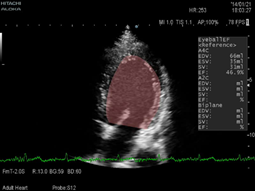

智能眼(EyeballEF)

ARIETTA智能眼技术已实现全实时状态下全自动测量并计算心功能参数,尤其在麻醉、心外科手术、药物实验、心率失常等领域独领风骚。